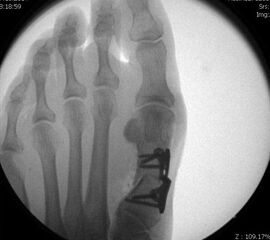

Die Stichinzisionen können genäht, aber auch nur mit Steristrips verschlossen werden. Im Anschluss erfolgt die Anlage eines sterilen Verbandes unter Miteinbeziehung der Zehenzwischenräume, mit einer leichten Kompression im Bereich der Metatarsalia durch eine Kohäsivbinde wie z.B. Coban®. So kann das Alignement gesichert werden. Sollten die DMMO´s als alleinige Maßnahme durchgeführt worden sein, kann der Patient direkt postoperativ in einem post-OP Schuh mit steifer Abrollsohle voll belasten. Der Patient muss darüber informiert sein, dass auch nach Entfernung des Wundverbandes die Elastokompressivverbände im Metatarsalebereich bis Abschluss der 6.postOP Woche regelmäßig anzulegen sind. Die Anlagetechnik sollte mit dem Patienten bereits präoperativ geübt werden. Bei Patienten mit geringer Compliance ist die Indikation für eine DMMO mit der Notwendigkeit eines über mehrere Wochen lückenlos zu tragenden Elastokompressivverbandes kritisch zu prüfen; engmaschigere Nachkontrollen als bei offener Vorgehensweise sind bis Ende der 6.post OP Woche nötig.

• Bei DMMO als isoliertem OP-Verfahren schmerzadaptierte Belastung im post-OP Schuh sofort möglich, bei zusätzlichen Eingriffen im Fußbereich Belastung in Abhängigkeit von diesen

• Röntgenkontrolle nach 14 Tagen und nach 6 Wochen